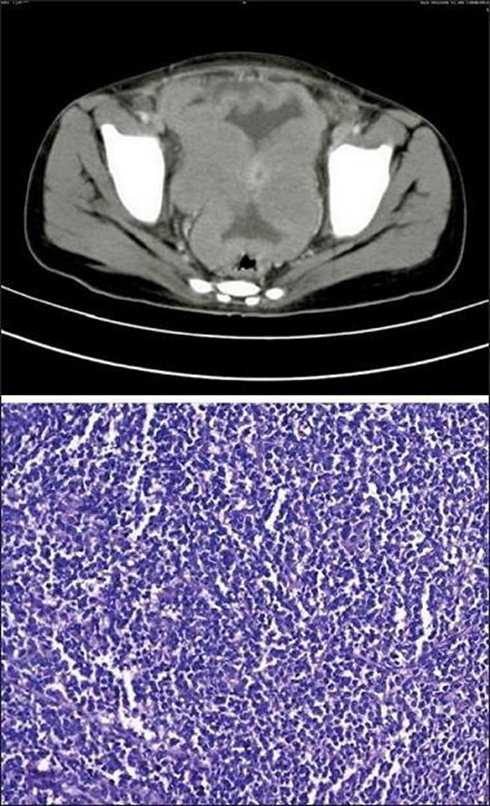

There are rare cases in the literature describing ovarian lymphoma which, although mimicking ovarian cancer, are diagnosed preventively, avoiding surgery. This aspect is well highlighted by Cyriac et al [11] who described the presence of Burkitt’s lymphoma in a 13-year-old patient, who, thanks to the use of CT, which highlighted the bilateral solid masses with peritoneal and omental deposits and the subsequent biopsy which detected positivity for CD45, CD20, CD10 and CD79 (Figure14), she was subjected to the LMB 89 therapeutic protocol obtaining a complete remission of the masses and remaining stable in the following 6 months of follow-up -up. Given the young age of the patient, this case highlights how chemotherapy treatment of lymphoma alone can avoid radical surgery. Another example of correct diagnosis is reported by Yamada [35], who describes a case of ovarian malignant lymphoma manifesting as advanced ovarian cancer.

Figure 14: The CT image highlights two solid and bilateral ovarian masses, with the presence of omental deposits and peritoneal implants. The immunohistochemical image obtained after biopsy highlights a proliferation of atypical lymphoid cells with little cytoplasm, nuclei with aggregated chromatin and many small nucleoli showing a high mitotic count.